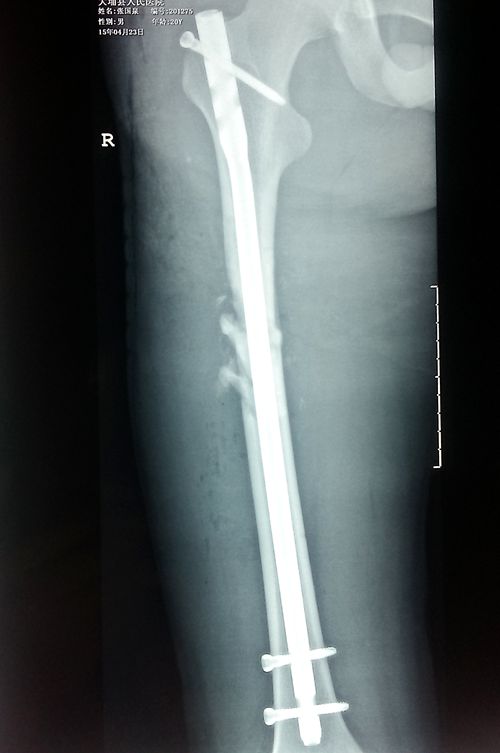

手术后

闭合复位磁力导航髓内钉内固定治疗股骨干骨折优点:

1、磁力导航定位器应用于交锁髓内钉远端锁钉,操作简单,定位准确,大大提高了远端锁钉的成功率;

2、磁力导航下完成交锁髓内钉的远端锁钉,彻底摆脱对C臂机的依赖,减少了放射损伤,降低了医疗成本;

3、磁力导航定位器的改进减少了打孔数量,减轻了手术创伤,有利于创伤面的愈合;

4、磁力导航定位器不破坏骨骼的血运,骨折愈合快,固定牢靠,不容易断钉致内固定装置失效;

5、髓内钉能很大程度上降低股骨干的应力,能早期功能锻炼及扶拐下地行走,减少关节僵硬发生率;

6、髓内钉内固定术符合生物固定(BO)原理,切口小,对软组织的影响小,降低了术中失血量及术后感染率,体现了微创原则,具有广阔的推广应用前景。(外一科 饶海军)